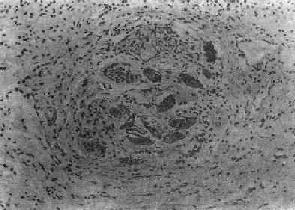

图19-6 血吸虫病之晚期急性虫卵结节

坏死区及嗜酸性粒细胞浸润范围缩小,其周围出现放射状排列的类上皮细胞层